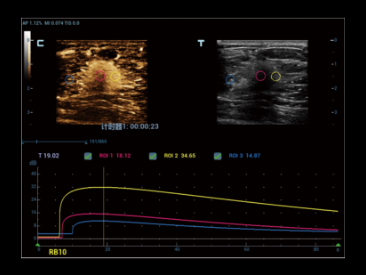

Potenciada por la tecnologĂa ZST+ y la ecografĂa de contraste mejorada (CEUS) basada en ondas planas, la HiFR CEUS permite que la ecografĂa de contraste mejorada ultrarrĂĄpida, para la visualizaciĂłn de la estructura vascular y perfusiĂłn en fase arterial, funcione como una herramienta complementaria de UWN+ (ultra-wideband nonlinear contrast imaging).

Caso HiFR CEUS: HNF de hĂgado

*No se recomienda aplicar HiFR CEUS en fase de retardo o en una regiĂłn de 10 cm de profundidad